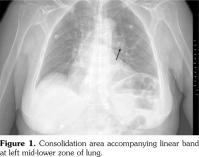

A 60-year-old female patient with no chronic disease except epilepsy which has been under control with oxcarbazepine and levetiracetam for 20 years applied to hospital. She received intravitreal bevacizumab injection (1.25 mg/0.05 mL) for age related macular degeneration at a private clinic and four days after this treatment, painful lesions emerged in her mouth accompanied with fever. She was admitted to the internal medicine clinic with these complaints and took diagnosis of febrile neutropenia. In spite of meropenem and amikacin treatment for four days, fever and neutropenia did not resolve; so, the patient was referred to our unit. On physical examination, her body temperature was 39.4 °C, multiple ulcers and white plaque lesions were observed in her mouth, and rales were present in the left lower lung zone compatible with pneumonia. X-ray revealed consolidation area with irregular borders at the middle zone of the left lung (Figure 1). The laboratory findings were as follows: white blood cells (WBC) 0.7 K/μl, neutrophils (absolute neutrophil count; ANC) 0.05 K/μl, platelets (PLT) 411 K/μl, hemoglobin (Hgb) 10.3 g/dL, C-reactive protein (CRP) 348.9 (0-5) mg/L, erythrocyte sedimentation rate (ESR) 101 mm/hour, procalcitonin 3.4 μg/mL (<0.05 μg/mL), total protein 5.9 mg/dL, and albumin 2.5 mg/dL. After obtaining the routine cultures, meropenem (3x1 g intravenous), vancomycin (2x1 g intravenous), liposomal amphotericin B (150 mg intravenous), and filgrastim (granulocyte colony- stimulating factor analog, 30 MU subcutaneous) were commenced. Thorax computed tomography showed pleural effusion accompanied by basal consolidation area and fibrous bands in the left lung compatible with pneumonia (Figure 2). On the fourth day of the treatment, patient’s fever and other clinical symptoms had not improved and laboratory results were as follows: WBC 1 K/μL, ANC 0.1 K/μL, Hgb 8.4 g/dL, PLT 535 K/μL, CRP 144 mg/L, ESR 140 mm/hour, and procalcitonin 2.24 μg/mL. Patient’s sputum culture yielded Stenotrophomonas maltophilia susceptible to trimethoprim/sulfamethoxazole and levofloxacin. Previous antibiotics were discontinued and trimethoprim/sulfamethoxazole and levofloxacin were started. Besides antibiotic therapy, anti-epileptic regime was maintained. The infectious agents which can cause neutropenia were also excluded. Antinuclear antibodies were detected as positive (++) by immunofluorescence assay at 1/100 titration and homogenous pattern. Also, anti-double stranded deoxyribonucleic acid was positive (+++) by immunoblotting techniques. In urinalysis, proteinuria was detected. Following the detection of protein in urinalysis, protein in 24 hour urine was measured as 735 mg. At the fifth day of the treatment with trimethoprim/ sulfamethoxazole and levofloxacin, patient’s body temperature returned to normal and clinical symptoms improved. Laboratory results were as follows: WBC 7.9 K/μL, ANC 4.5 K/μL, Hgb 8.5 g/dL, PLT 205 K/μL, CRP 10.5 (0-5) mg/L, ESR 36 mm/h, procalcitonin 0.08 μg/mL, blood urea nitrogen 27 mg/dL, and creatinine 0.8 mg/dL. An evaluation of kidney biopsy performed due to significant proteinuria revealed mild staining with immunoglobulins and complements. Kidney biopsy was found compatible with class III + class V lupus nephritis.